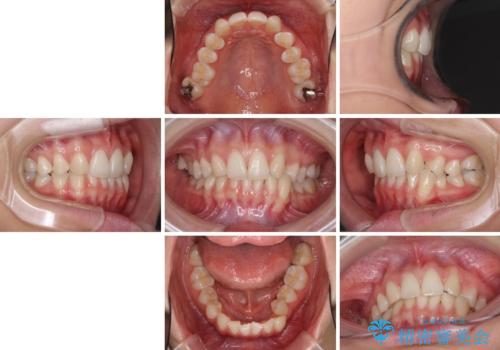

上顎前歯が2本欠損 インビザラインによる叢生の解消

- 深い咬み合わせと前歯のデコボコを気にして来院された患者様です。

上顎前歯2本が欠損しているため、妥協的なゴールを設定しインビザラインで矯正治療を行うこととしました。

上下前歯の大きさのアンバランスにより、深い咬み合わせと奥歯の咬みにくさがなかなか解決されず、治療に長期間を要することとなりました。